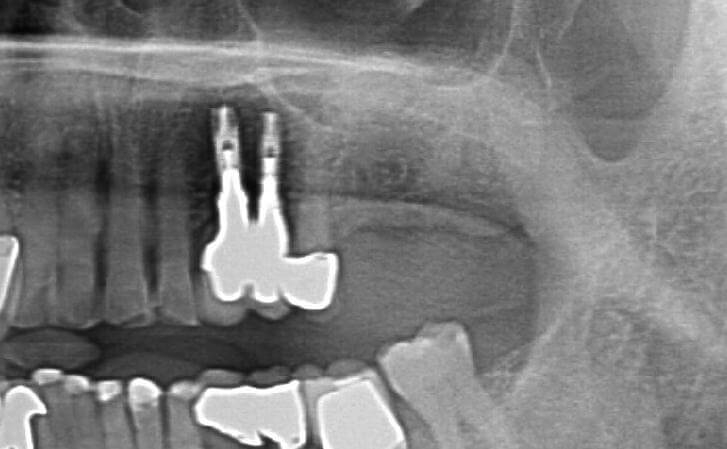

Patient lost upper right molar due to decay. Had insufficient bone for implant placement without a bone graft. Underwent Internal Sinus lIft procedure with Immediate Implant Placement

Patient had upper right molar extracted. CT scan revealed insufficient bone volume to place implant as is. Pt underwent INTERNAL SINUS LIFT procedure at the same time as Implant placement. This allowed bone grafting and implant placement to be performed together. State of the Art Surgery

The patient had a decayed molar #14. It was removed and an immediate implant was placed in conjunction with an Internal Sinus lift procedure.